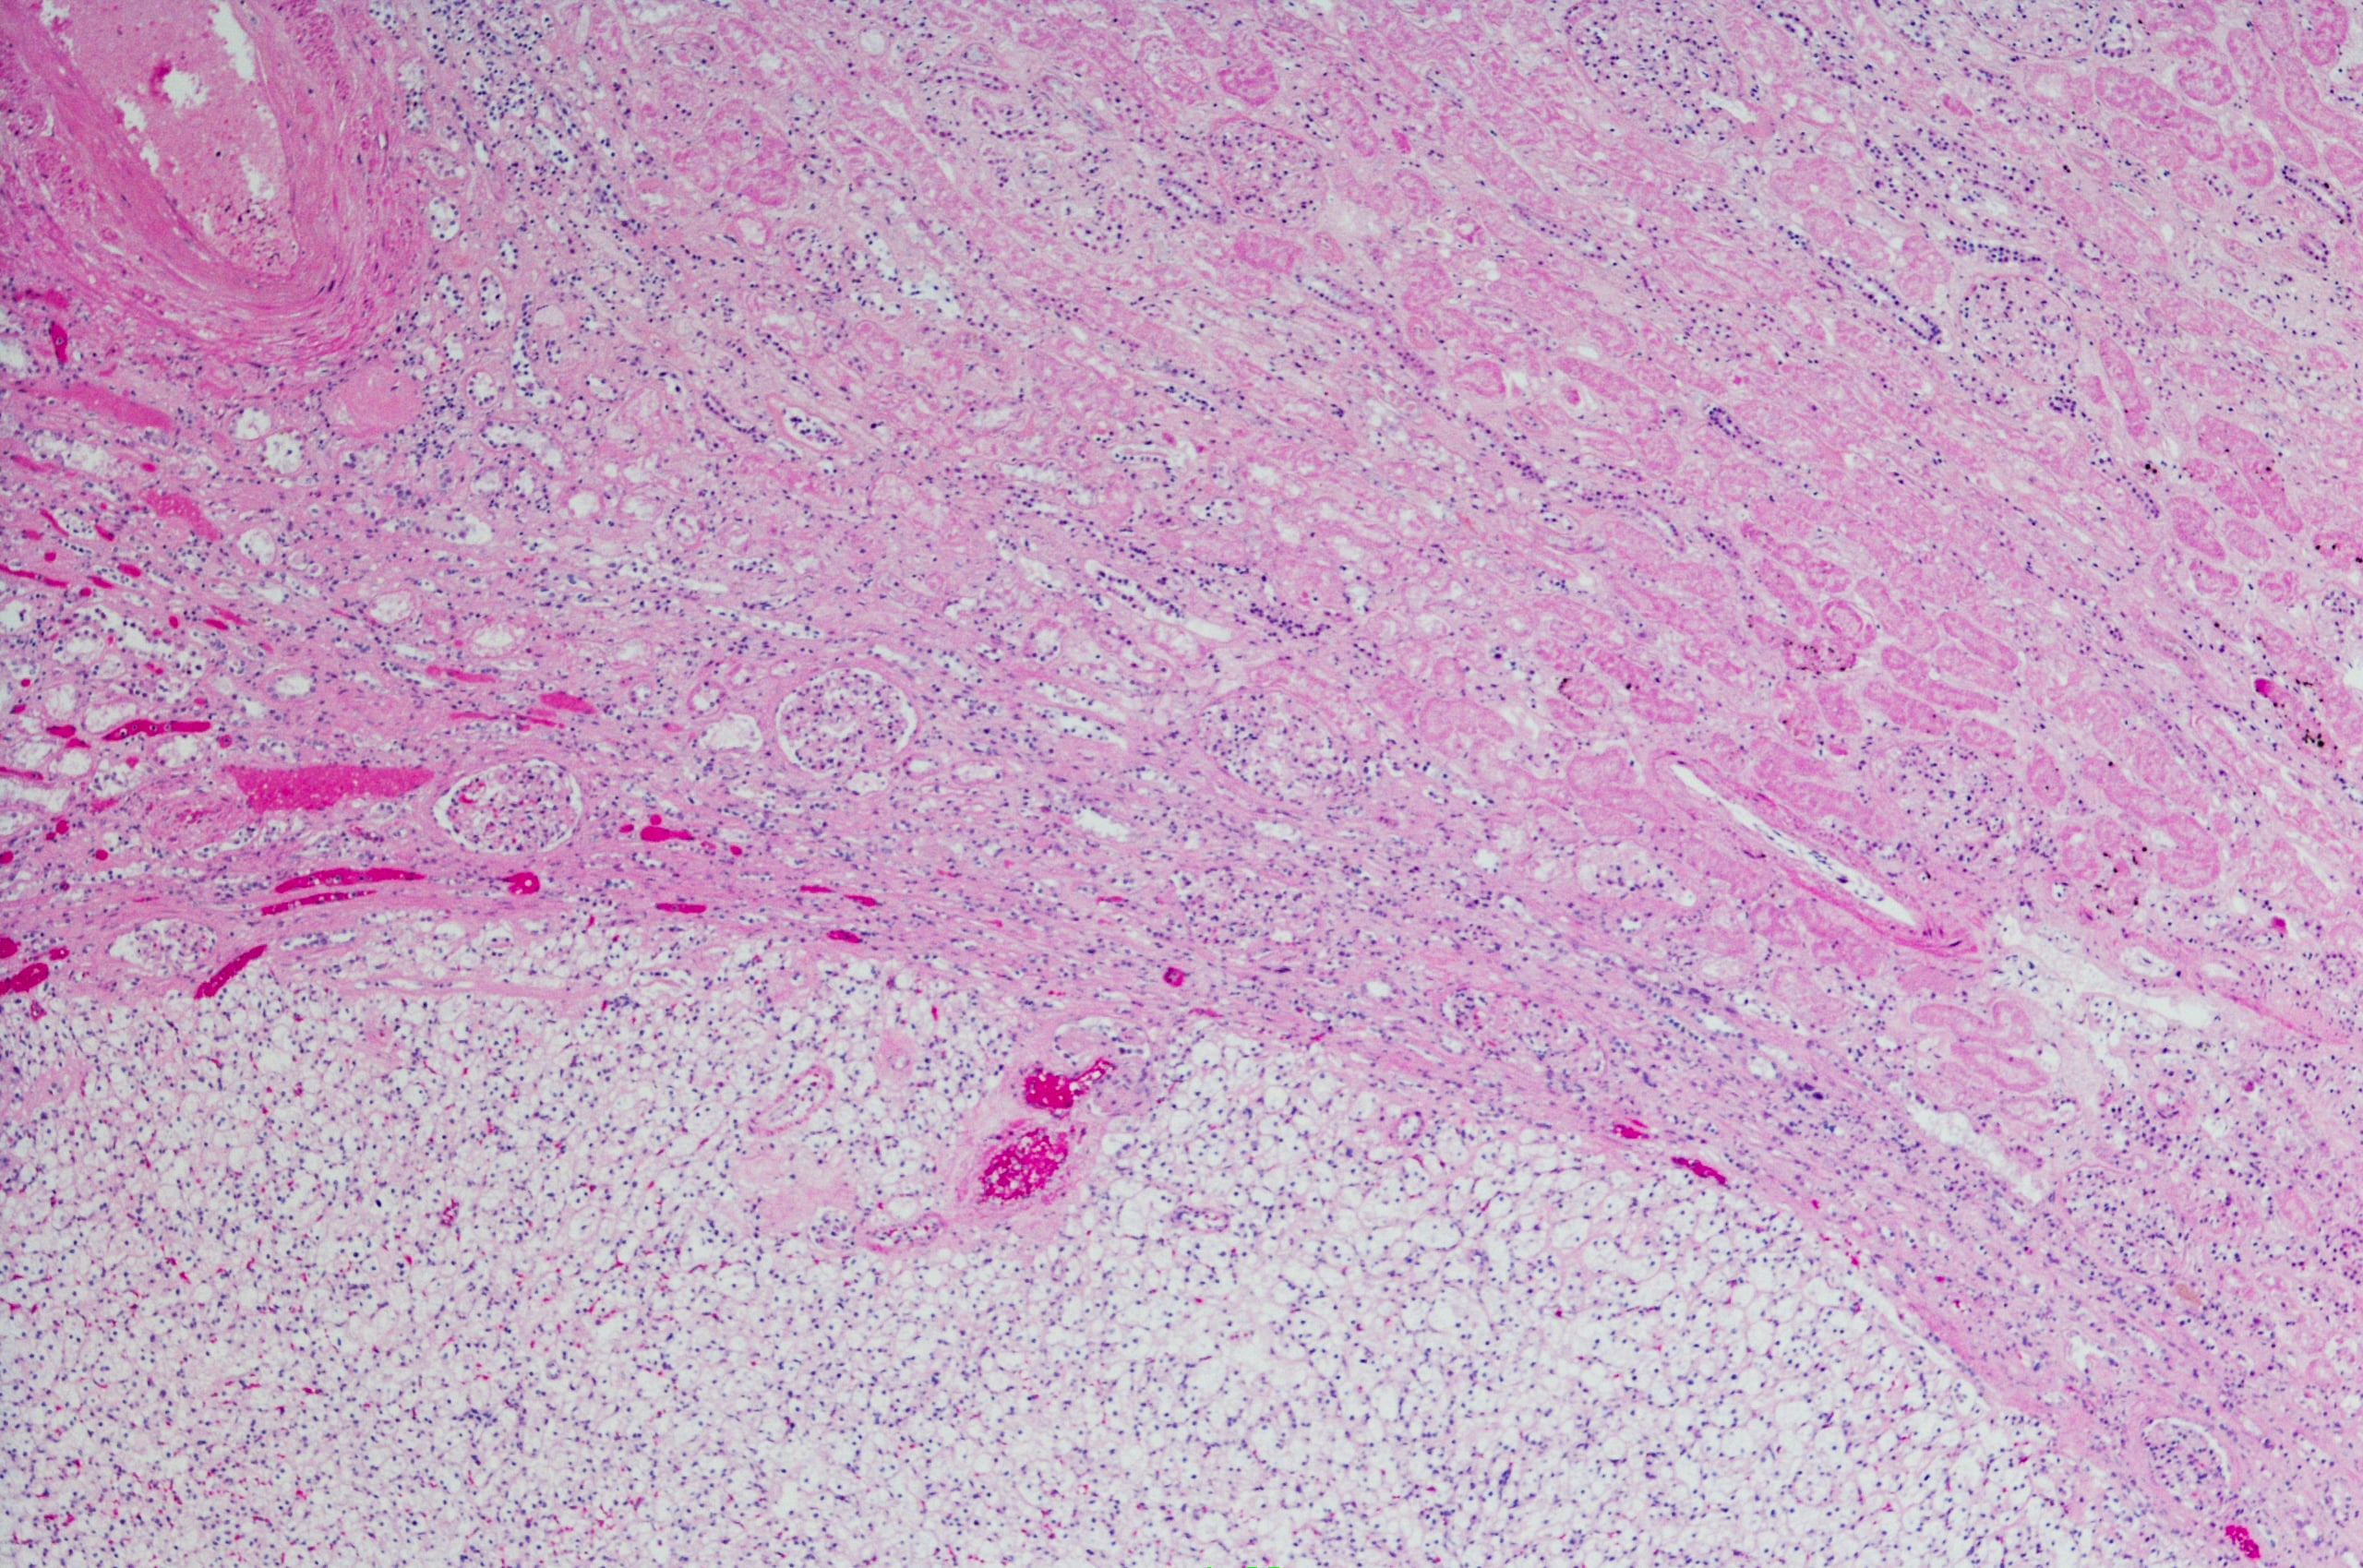

Multilocular cystic renal cell carcinoma (MCRCC)